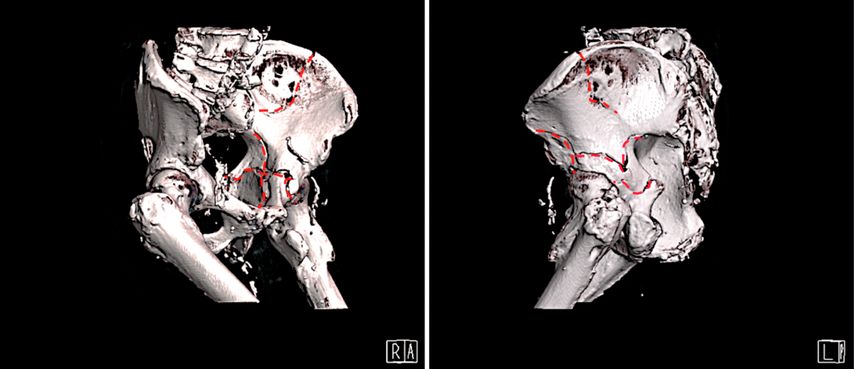

Die präoperative Planung erfolgt CT-gestützt mit 3D-Rekonstruktionen (Abb. 2). Besonderes Augenmerk liegt auf der Beurteilung des knöchernen Areals oberhalb des Foramen ischiadicum majus („sciatic buttress“), da dies den Korridor für die zentrale Ileumschraube darstellt. Zudem sollte die ursprüngliche Hüftzentrumslage wiederhergestellt werden, um ein biomechanisch günstiges Operationsergebnis zu erzielen.

Abb. 2: 3D-Rekonstruktion einer vorderen Pfeiler-/hinteren Hemiquerfraktur (gestrichelte Linie: Frakturausläufer)